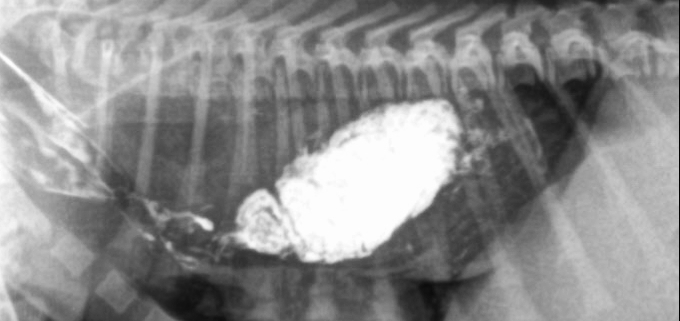

Cistoscopia litiasis uretral